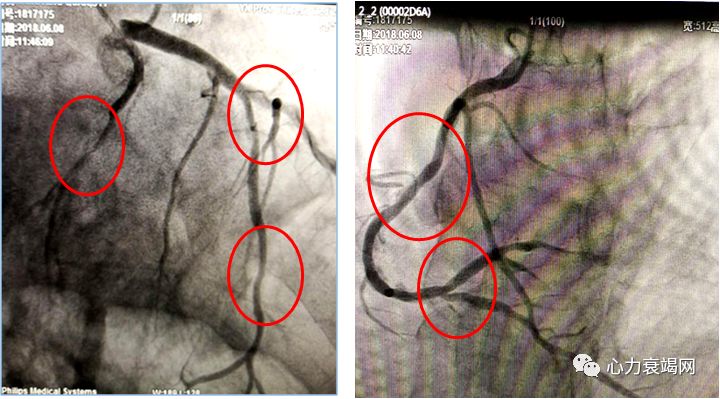

3、但该病例可能存在一个疑问,患者全心增大,冠脉造影可见LCX高度狭窄,LAD及RCA轻中度狭窄,患者的临床诊断考虑是缺血性心肌病还是扩张性心肌病还值得思考?另外患者在临床治疗过程中应用利尿剂的同时,如果加用小剂量多巴胺扩张肾动脉,及加用正性肌力药物如左西孟旦等可能会得到更好的治疗效果。